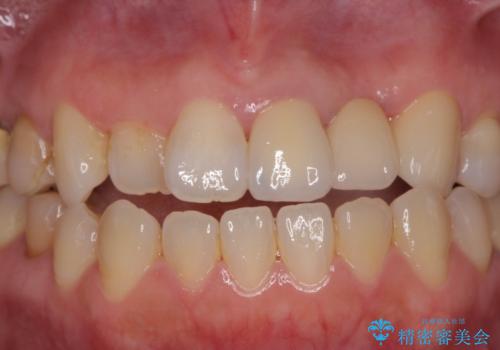

- 前歯がクラグラして噛めないことの改善を求めて来院されました。

X線撮影や歯周組織検査から、クラウン下の虫歯の再発や歯の破折が疑われる状況でした。

左上2は、クラウン メタルコアの除去を行ったところ虫歯の再発や亀裂を認め、長期的な予後の期待が難しいことから抜歯を行い

ブリッジで審美性の回復を行っていく運びとなりました。

- 39.6万円(ジルコニアクラウン×3・仮歯×3)費用は治療当時の料金となります